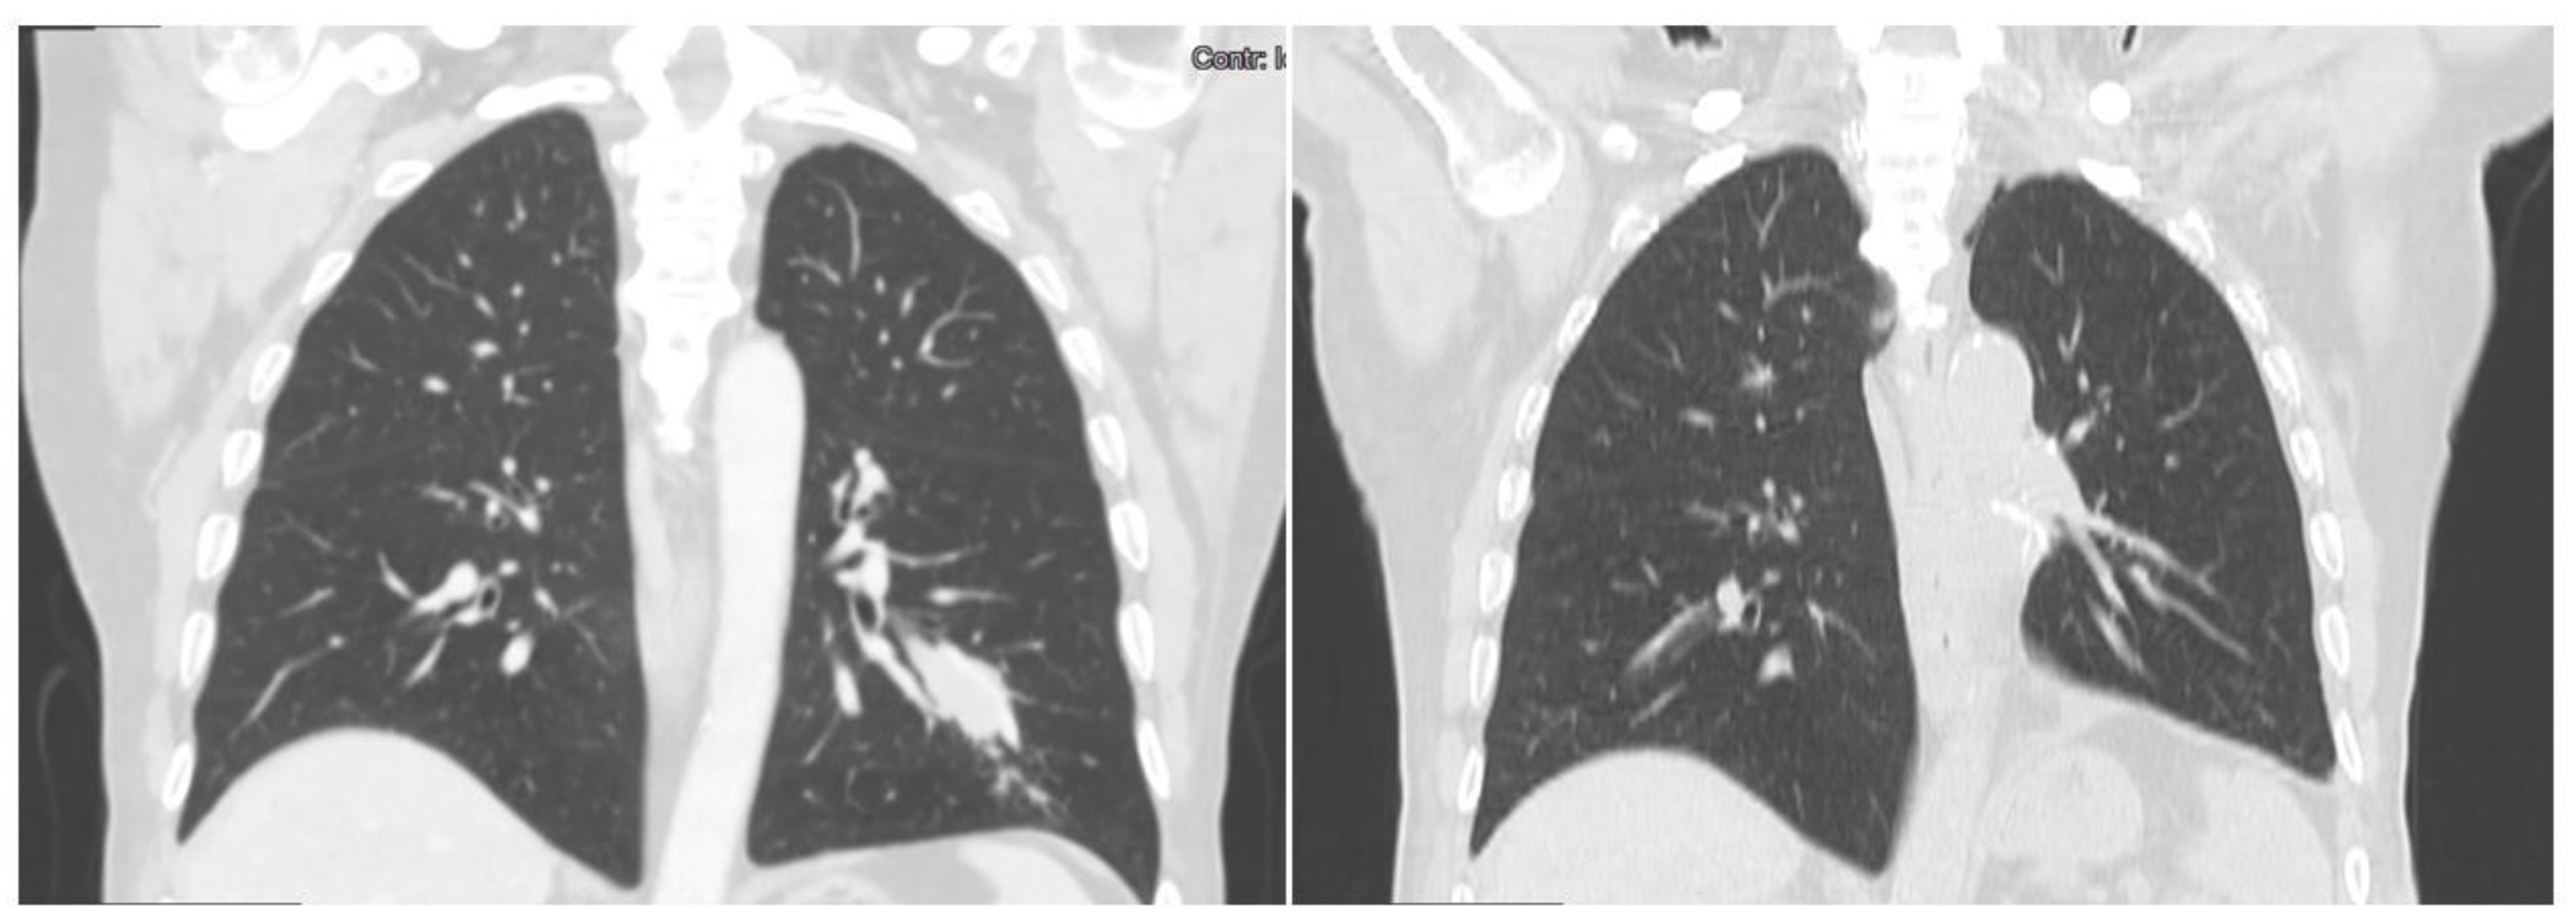

3.1. Case 1

3.2. Case 2

3.3. Case 3